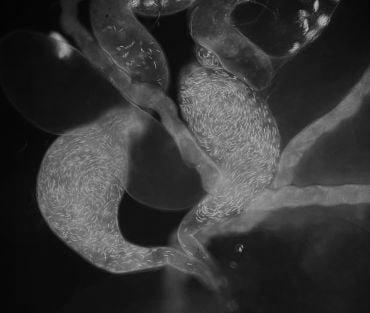

Sperm tagged with green fluorescent protein in the sperm storage organ of a female Drosophila fruit fly. Credit: Krish Sanghvi.

Sperm tagged with green fluorescent protein in the sperm storage organ of a female Drosophila fruit fly. Credit: Krish Sanghvi.

Both male and female animals can store sperm as a reproductive strategy (in humans, sperm can last for several days in females but the effects of such storage are unknown). In males this ensures enough sperm are present for mating, and in females this can enable reproduction even when males are scarce. However, the study found a striking difference in the rate of sperm deterioration in males versus females. In the species studied, females are generally better than males at preserving sperm quality long-term.

‘This likely reflects the evolution of female-specific adaptations, such as specialised storage organs that provide antioxidants to extend sperm viability’, explained senior author Dr Irem Sepil (Department of Biology, University of Oxford). ‘These organs often secrete reproductive fluids to nourish sperm and could provide unexplored avenues for biomimicking technology to improve artificial sperm storage in the future.’

Lead author Dr Krish Sanghvi (Department of Biology, University of Oxford) added: ‘Ejaculates should be viewed as populations of individual sperm which undergo birth, death, ageing and selective mortality. The rates of these demographic processes can differ in males and females, mediating the “demographic” structure of sperm populations and sex-specific differences in sperm storage effects.’